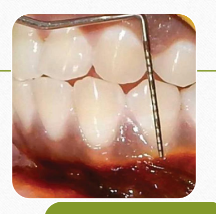

TRANSGINGIVAL PROBING / BONE SOUNDING

Probing after the site is anesthetized

Probe introduced until it reaches the bone

Done as a presurgical evaluation to assess the bone defect